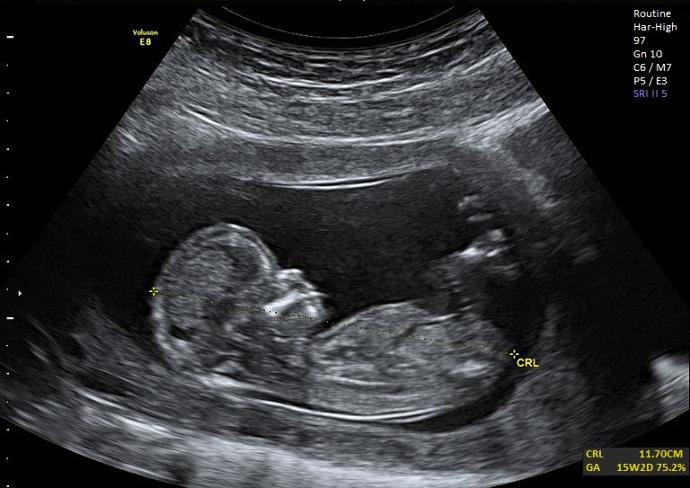

When we were going to check this with my doctor, I did a new ulrasound during the ultrasound the baby decided to curl up.

During the ultrasound my baby kicked, and I was so happy, I have a healthy baby who's growing healthy and strong, the doctor said there are some pregnants who feels the kicking and moving pretty early especially the thin preg..in few weeks I'll know what's my baby gender, which makes me so excited, my baby is growing tall, and she/he moved because she/he can sense light now, I did the experience again once I was home I used a flash light on my tummy and she/he moved lol so cute